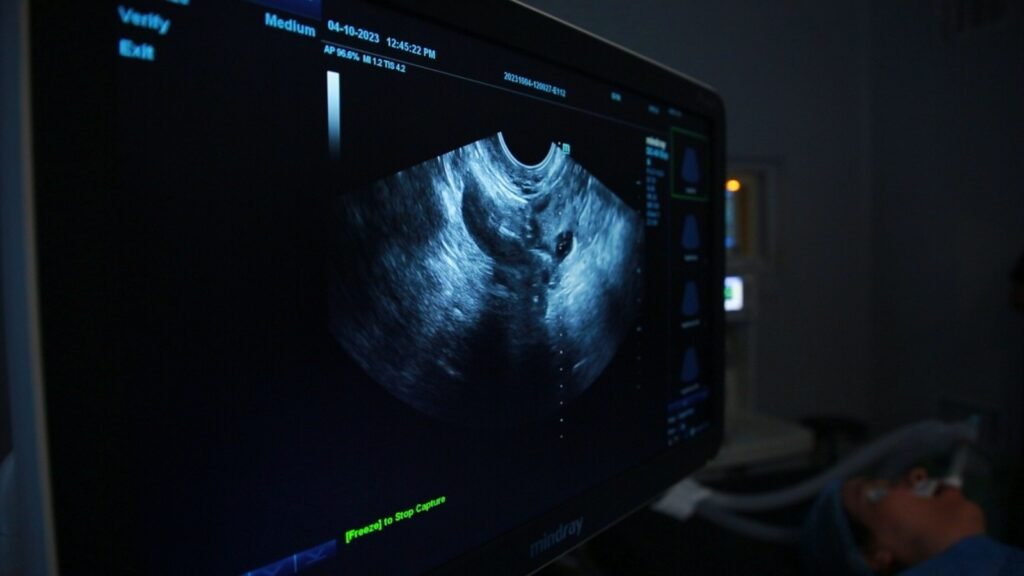

الطبيبة إسراء النحاس، إحدى الطبيبات المتخصصات بأجراء تلك العمليات داخل أحد المراكز في العاصمة، تقول إن الاقبال على إجراء هذه العمليات، زاد بشكل لافت، لاسيما مع امتلاك الخبرة لدى الكوادر الطبية المحلية، ودخول التقنيات الحديثة، وقلة تكاليفها مقارنة بإجرائها خارج العراق.

النحاس قالت إن فوائد تلك العملية تتنوع بين الباحثين عن الحصول على طفل ذكر، كما هو حال المجتمع، وبين المحرومين من الإنجاب والذين تمثل لهم هذه العمليات فرصة مثالية.